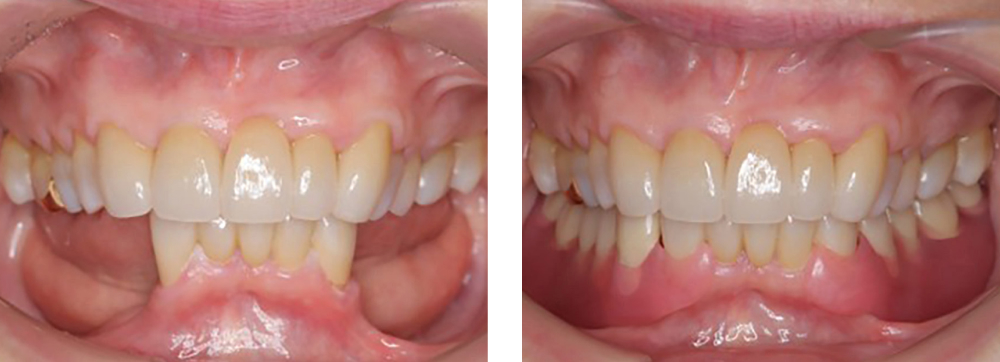

全顎保険治療

術前

術後

| 治療内容 | 全顎的に保険内で治療を行った |

|---|---|

| 治療期間・回数 | 約2.5年・約50回 |

| 費用 | 保険適用となります |

| リスク・副作用 |